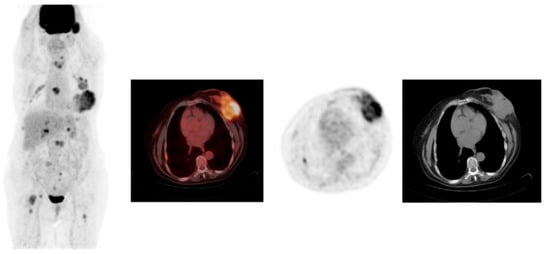

- Dijkers, E.C.; Oude Munnink, T.H.; Kosterink, J.G.; Brouwers, A.H.; Jager, P.L.; De Jong, J.R.; Van Dongen, G.A.; Schroder, C.P.; Lub-de Hooge, M.N.; de Vries, E.G. Biodistribution of 89Zr-trastuzumab and PET imaging of HER2-positive lesions in patients with metastatic breast cancer. Clin. Pharmacol. Ther. 2010, 87, 586–592. [Google Scholar] [CrossRef]

- Gebhart, G.; Lamberts, L.E.; Wimana, Z.; Garcia, C.; Emonts, P.; Ameye, L.; Stroobants, S.; Huizing, M.; Aftimos, P.; Tol, J.; et al. Molecular imaging as a tool to investigate heterogeneity of advanced HER2-positive breast cancer and to predict patient outcome under trastuzumab emtansine (T-DM1): The ZEPHIR trial. Ann. Oncol. 2016, 27, 619–624. [Google Scholar] [CrossRef]